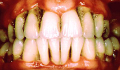

Outre la carie, les maladies parodontales, constituent le principal problème buccodentaire chez les adultes. Il s’agit d’une infection des gencives résultant en une destruction de l’os soutenant les dents. Elle est la plupart du temps précédée d’une gingivite (inflammation et saignement des gencives). Cette maladie est aggravée par une accumulation de plaque dentaire et de tartre pris entre la gencive et les dents. L’intervention d’un dentiste sera nécessaire pour guérir cette condition.

Le traitement parodontal vise à rétablir la santé des gencives. Il nécessite un détartrage sous anesthésie, soit l’enlèvement de la plaque dentaire et du tartre accumulés sur les dents et les racines afin de les rendre lisses et dépourvu de débris. Ceci entraîne l’arrêt de la perte osseuse et la guérison des gencives. Par la suite, il est important d’être suivi régulièrement chez le dentiste pour répéter le traitement afin d’éviter que le tartre s’accumule de nouveau et que la perte osseuse recommence. Aussi, des mesures d’hygiène rigoureuses par le patient sont nécessaires au maintien de la santé de l’os et des gencives supportant les dents.